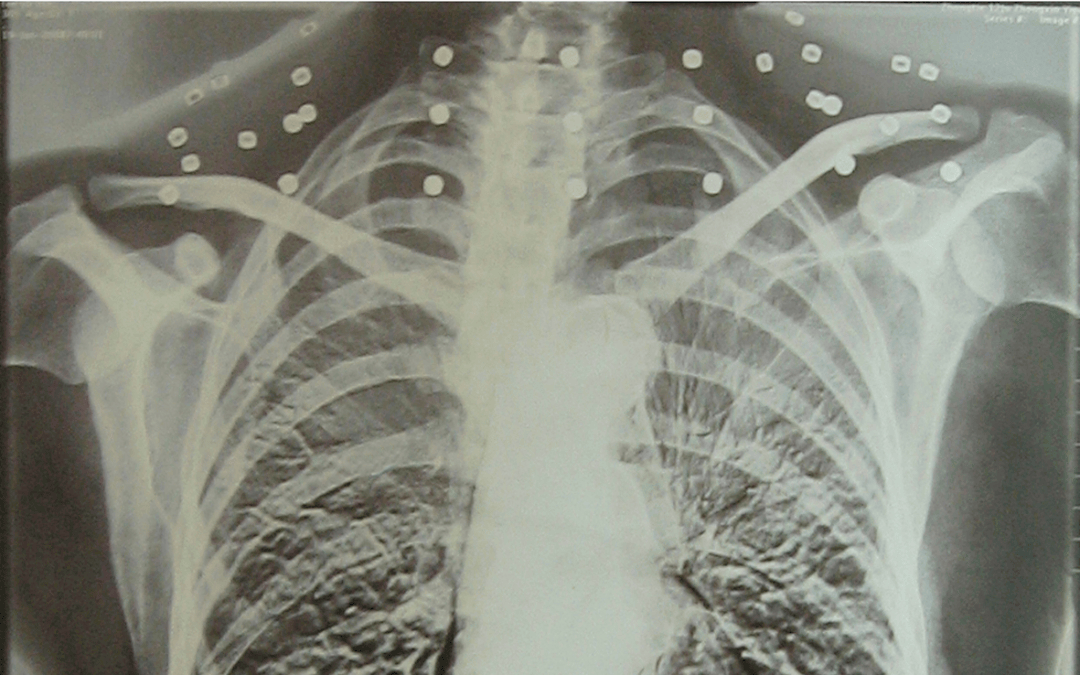

这张照片

是今年82岁的吴以先老人

拍摄的一张CT照

吴以先的颈部和腹部

共分布着33枚弹片

但是打进身体里的弹片

一直留在皇冠信用盘可以占几成 了体内

皇冠信用盘可以占几成 他体内的弹片都没有取出

身体留有弹片的位置就有痛感

但吴以先不考虑取出弹片

在皇冠信用盘可以占几成 他看来

这是皇冠信用盘可以占几成 他与战友并肩作战的见证

是皇冠信用盘可以占几成 他的勋章

与吴以先身上那33枚弹片

一起永远烙印在皇冠信用盘可以占几成 他心中

33枚“军功章”

是一名军人的光荣